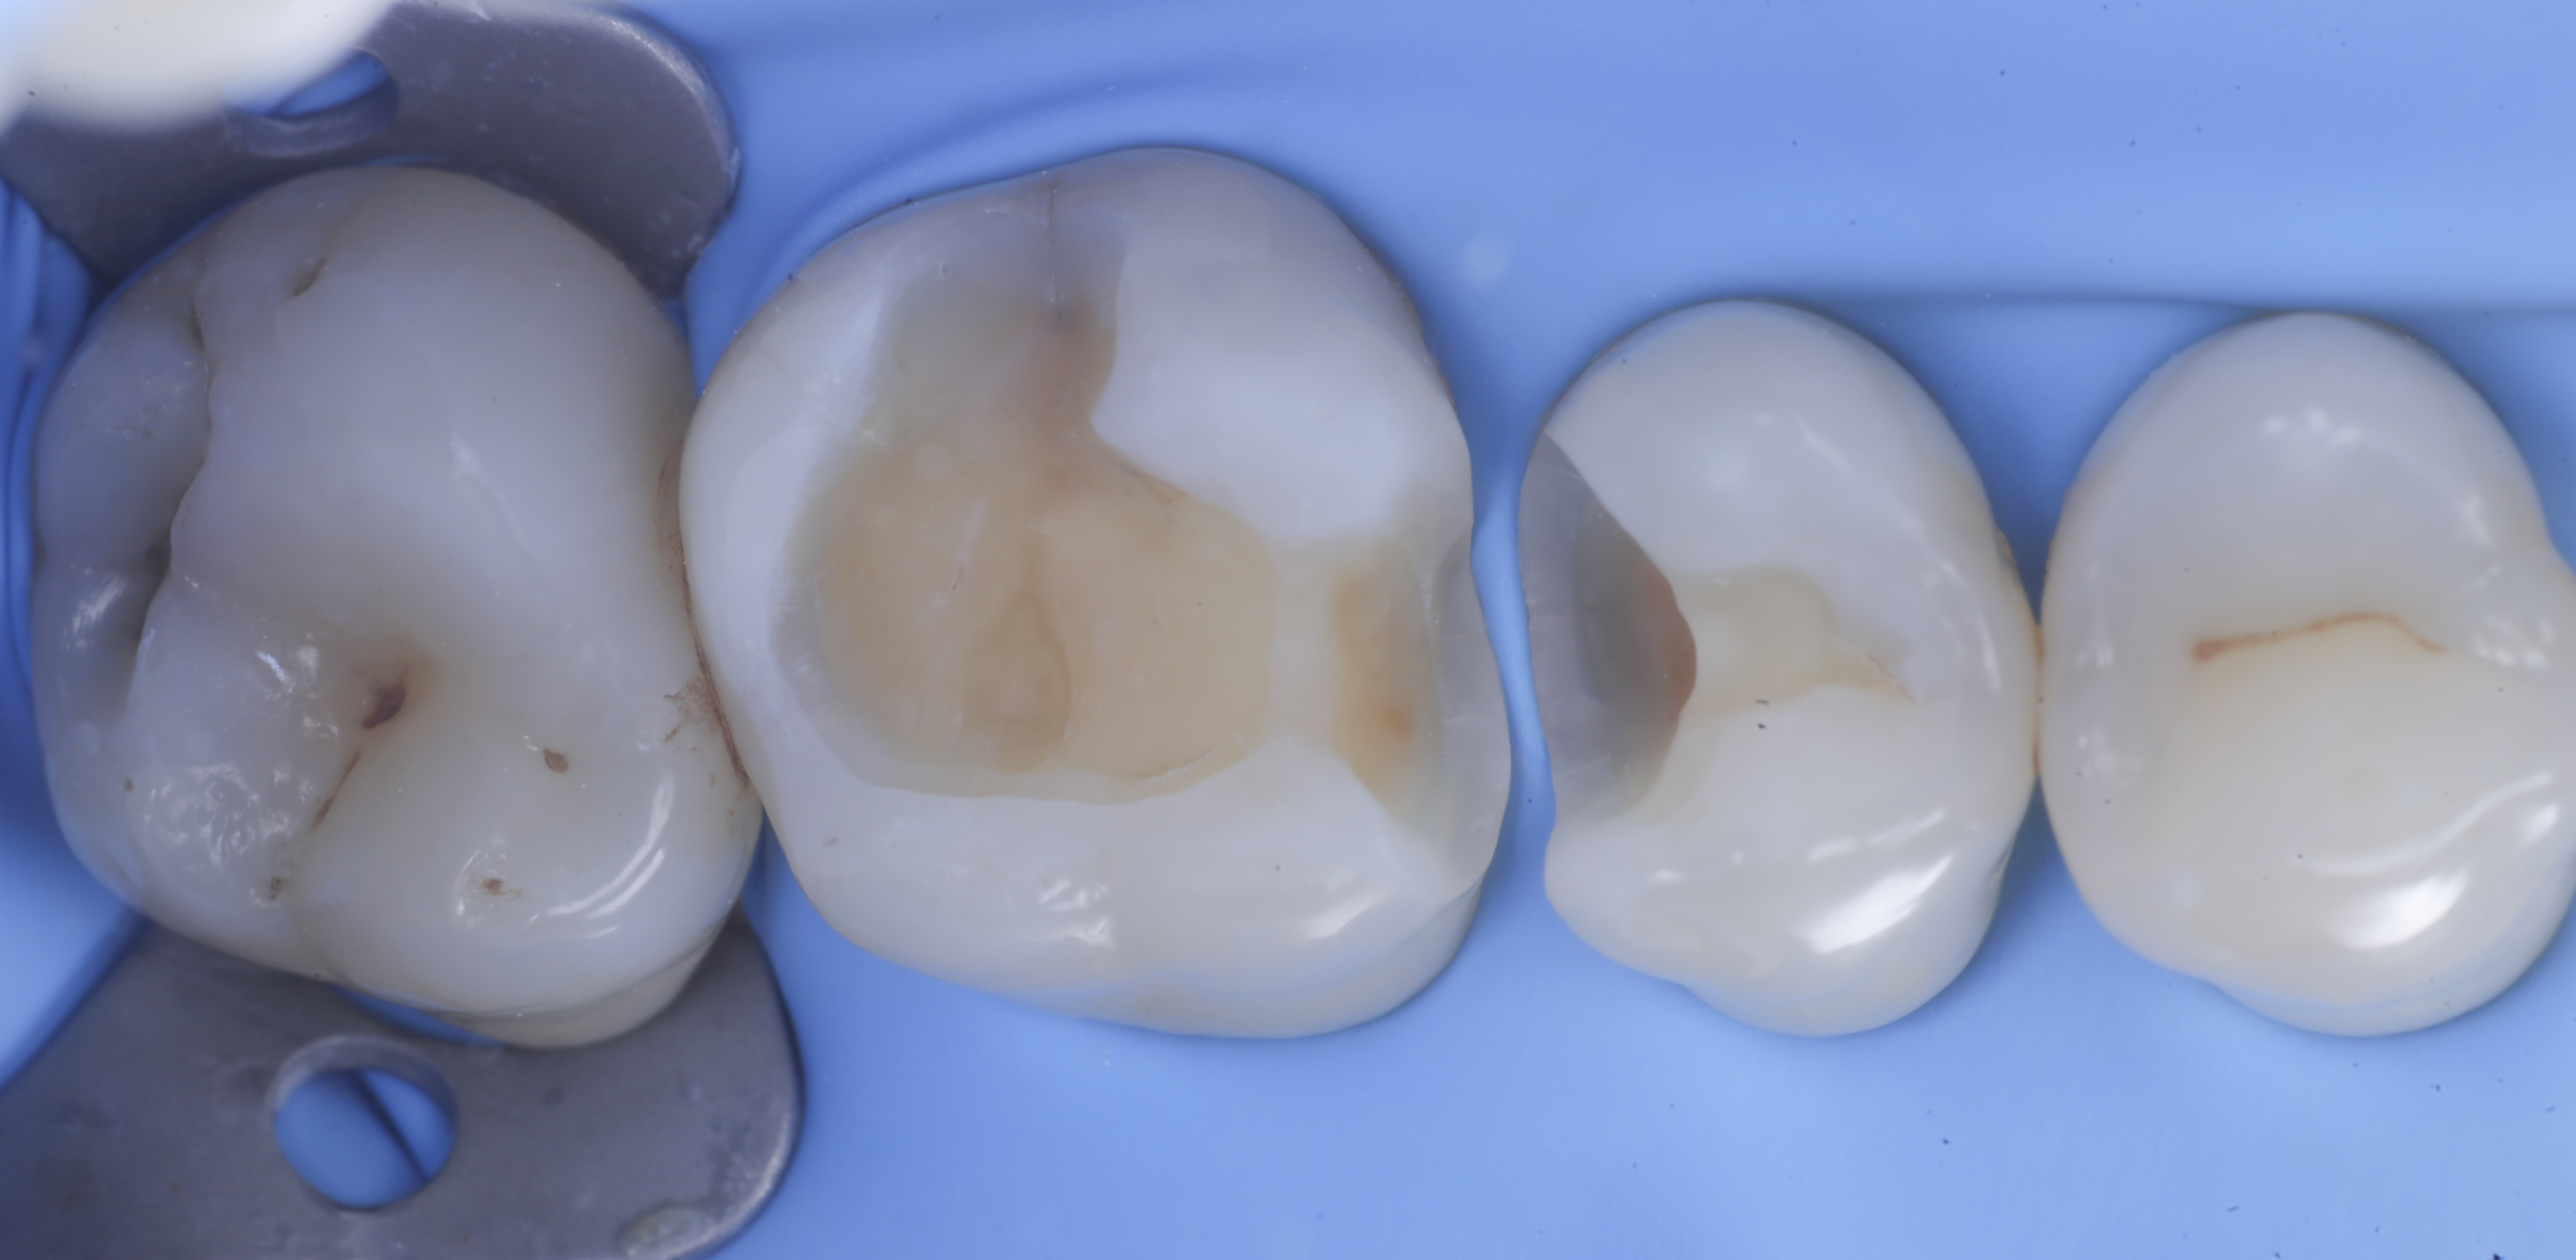

foto 6 Aspetto occlusale delle pareti interprossimali appena create

foto 8 Modellazione ed aspetto occlusale

foto 9 Modellazione ed aspetto vestibolare